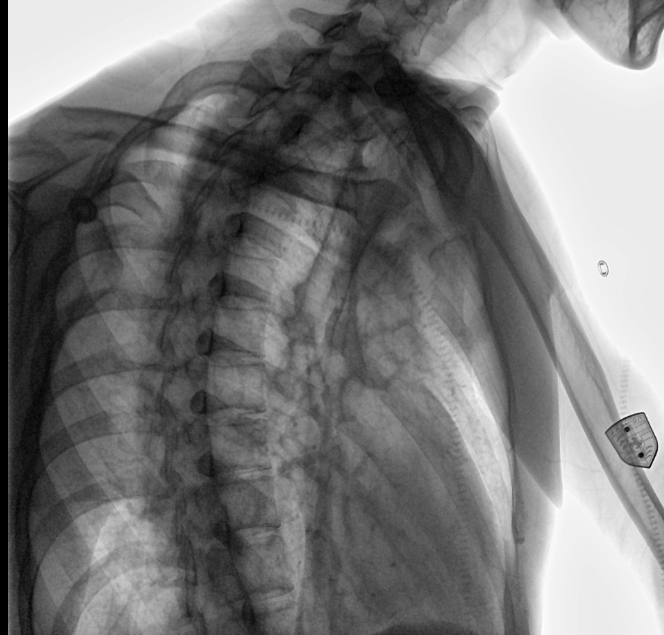

位于衡水市中醫(yī)醫(yī)院的動(dòng)態(tài)平板數(shù)字化X射線系統(tǒng)DTP571具備高速高清點(diǎn)片功能。這是一款對(duì)放射科十分友好的產(chǎn)品。因?yàn)樗迅咚俸透咔妩c(diǎn)片結(jié)合,既能方便影像技師有效地抓拍需要的病灶的影像,又能給予影像醫(yī)生清晰的影像進(jìn)行診斷

衡水市中醫(yī)醫(yī)院的放射科主任醫(yī)師于金厚主任為患者進(jìn)行檢查

衡水市中醫(yī)醫(yī)院的放射科主任醫(yī)師于金厚主任操作國(guó)產(chǎn)DR設(shè)備

動(dòng)態(tài)觀察診斷,實(shí)時(shí)高清點(diǎn)片